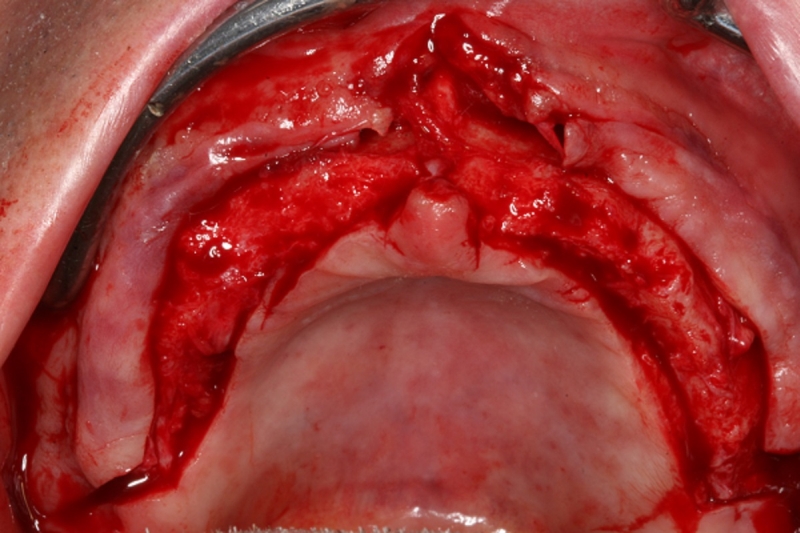

08/10 - Re-entry surgery in combination with vestibuloplasty to form the vestibulumCircular bone splitting with maxresorb® & collprotect® membrane - PD Dr. J. Neugebauer